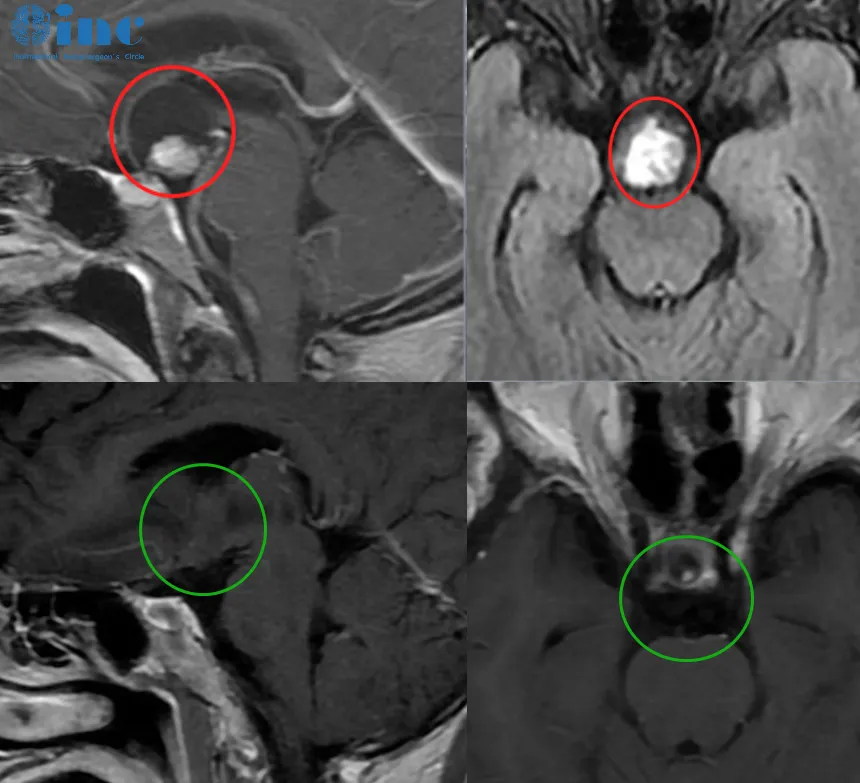

▲术前术后影像对比,红色为术前肿瘤位置,绿色为术后切除效果